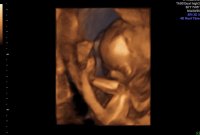

Og jeg er evig takknemlig for at alt ser helt perfekt ut på UL i dag med skikkelig anatomisk gjennomgang, fra hodet til tær, og alt som var fryktelig galt er helt perfekt nå. Er 12+2 i dag, men jordmor målte meg til 12+4, så termin rundt 28 april. Spent på om sykehuset finner det samme på ultralyd neste onsdag. Enn hvor glad jeg er for at jeg har en frisk lillebror i magen, så er jeg ett lite snev skuffet. Skuffet over at jeg ikke får min lille prinsesse Maja, som jeg alltid har drømt om. Vet at jeg blir like glad i lillebror som jeg er i storebror og gutt kan jeg jo, men jeg drømte liksom om å få en jente. Men min jente var syk…

21+4 og tiden går både fort og sent på samme tid…